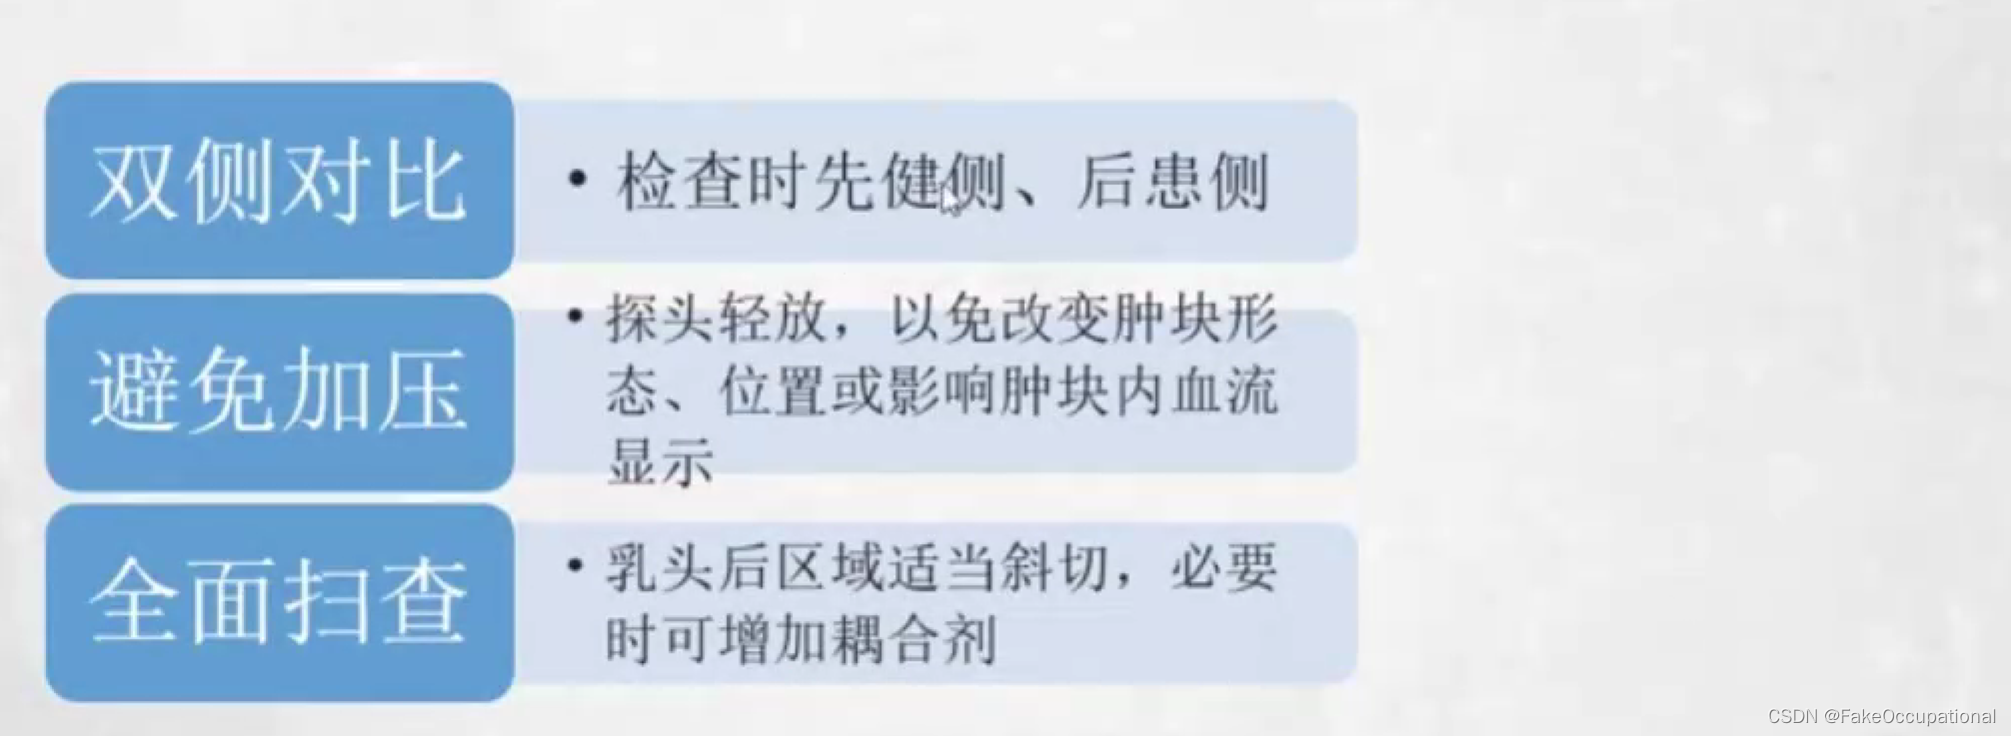

乳腺检查注意事项

- 双侧对比:检查时先健侧、后患侧

- 避免加压: 探头轻放,以免改变肿块形态、位置或影响肿块内血流显示,必要时加压

- 全面扫查: 乳头后区域适当斜切,必要时可增加耦合剂